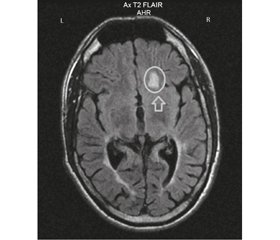

После развития первого эпилептического приступа при повторном МРТ-исследовании в возрасте 15 лет и на момент исследования отмечалось формирование свежих очагов в субкортикальных отделах правой лобной, правой затылочной и левой теменной долей (рис. 1).

/82-1.jpg) После развития первого эпилептического приступа при повторном МРТ-исследовании в возрасте 15 лет и на момент исследования отмечалось формирование свежих очагов в субкортикальных отделах правой лобной, правой затылочной и левой теменной долей (рис. 1).

После развития первого эпилептического приступа при повторном МРТ-исследовании в возрасте 15 лет и на момент исследования отмечалось формирование свежих очагов в субкортикальных отделах правой лобной, правой затылочной и левой теменной долей (рис. 1).